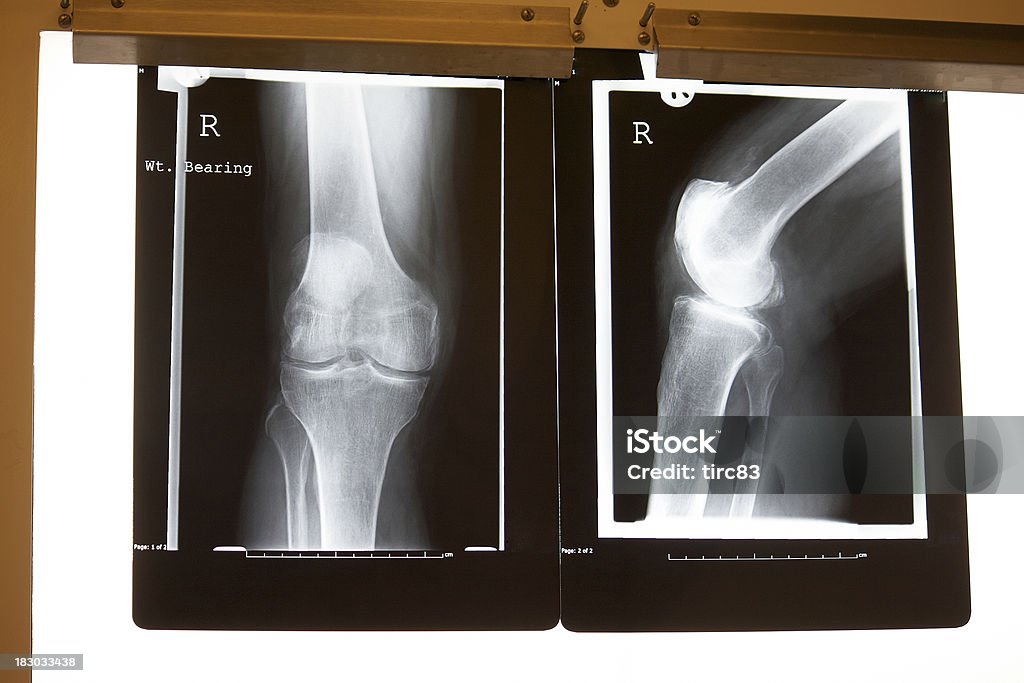

Get a medical evaluation – Request X-rays, MRIs, and metal level tests.

🩻 Symptoms of Joint Replacement Failure

Patients with defective joint implants often experience:

Persistent or worsening pain near the surgical site

Reduced range of motion

Limping or trouble walking

Grinding or clicking sounds

Swelling or warmth around the joint

If you’re experiencing any of these symptoms, consult your doctor immediately—and request diagnostic imaging or lab tests.